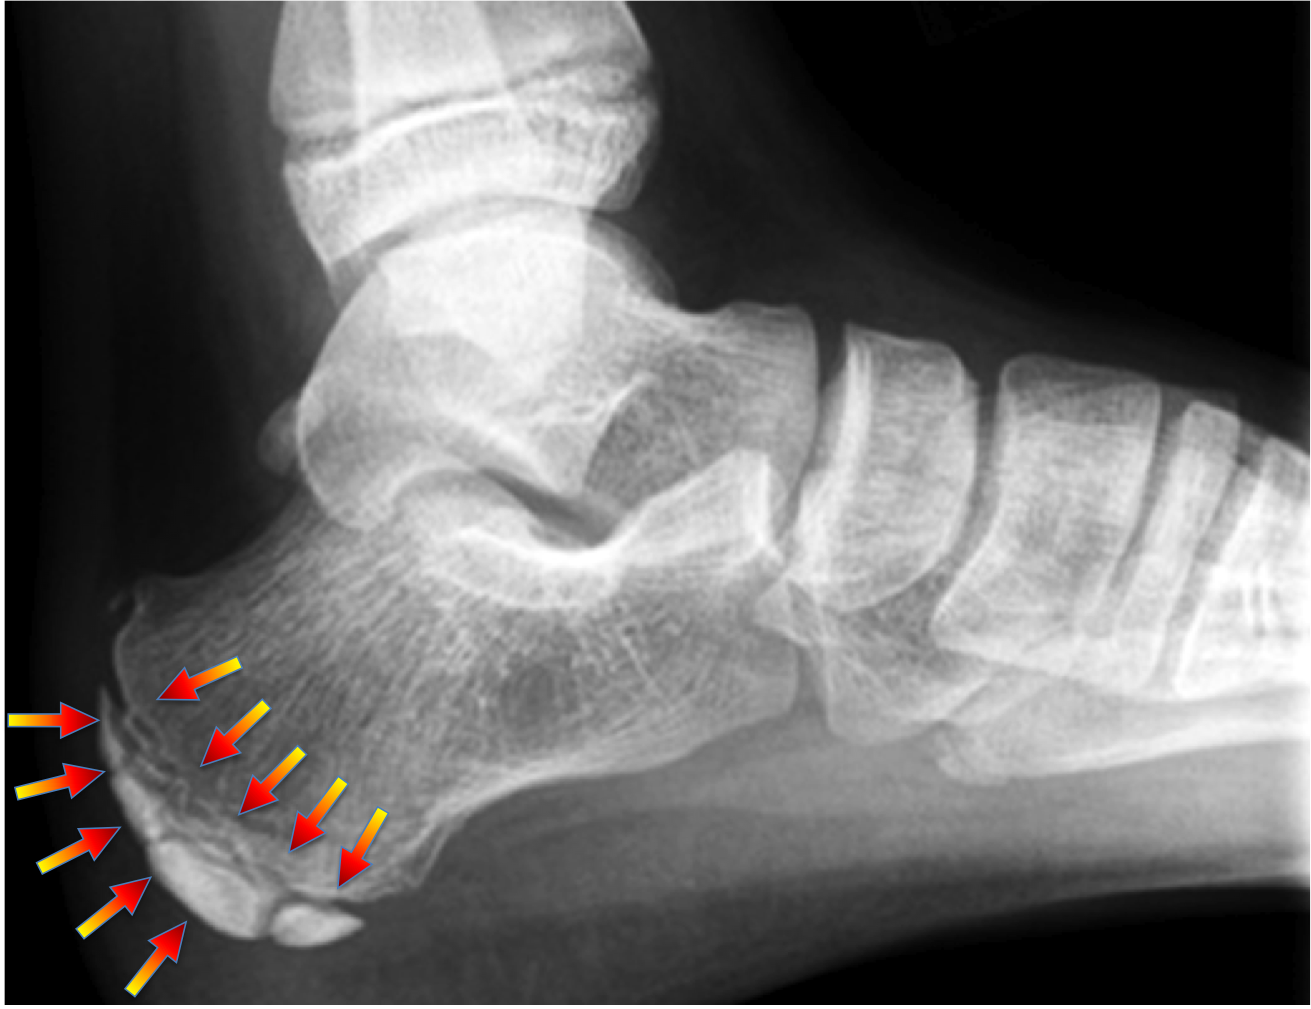

3. Osteocondrose do Calcâneo ( Doença de Sever ou Haglund-Sever ):

A osteocondrose do calcâneo ou doença de Sever acomete principalmente crianças entre 7 e 12 anos de idade e está relacionada com o aumento da atividade esportiva de impacto como o futebol, basquete, handebol ou vôlei.

Acomete seis vezes mais meninos do que meninas (6:1) e frequentemente é bilateral.

A principal queixa é a dor na região plantar do calcanhar que aumenta durante ou após a atividade esportiva. A criança pode começar a caminhar na ponta dos pés, evitando apoiar o calcanhar doloroso no chão e, consequentemente, reluta em praticar atividades de salto ou corrida.

Na avaliação clínica o principal sinal é a dor a palpação localizada na face plantar do calcanhar.

No exame radiológico a cartilagem de crescimento (fise) apresenta-se alargada, irregular e com sinais de esclerose e fragmentação óssea ao redor da lesão.

O tratamento é conservador, inicialmente com o uso de medicação analgésica e afastamento das atividades de impacto (corrida e/ou salto).

Se a dor inicial for intensa, a retirada do apoio com muletas e a imobilização com tala gessada ou bota imobilizadora podem ser usadas temporariamente.

Sessões de fisioterapia, visando principalmente o alongamento tendíneo da panturrilha, devem ser feitas após a melhora da dor intensa inicial.

É importante enfatizar que a osteocondrite do calcâneo (de Sever) é uma alteração autolimitada, isto é, possui um curso determinado, e não deixa deformidades ou sequelas para a vida adulta.